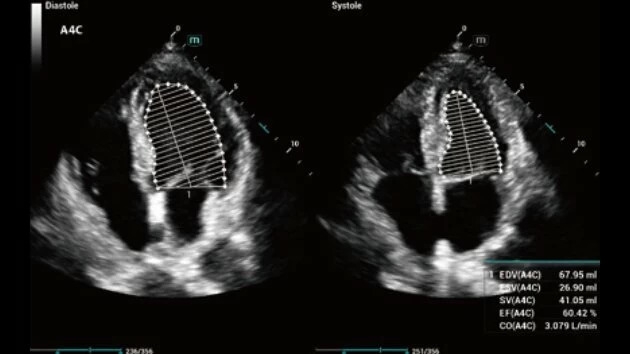

- Высокое разрешение изображений для точной диагностики

- Расширенный набор диагностических функций

- Широкий спектр клинических исследований

- Расширенные возможности визуализации различных органов и тканей